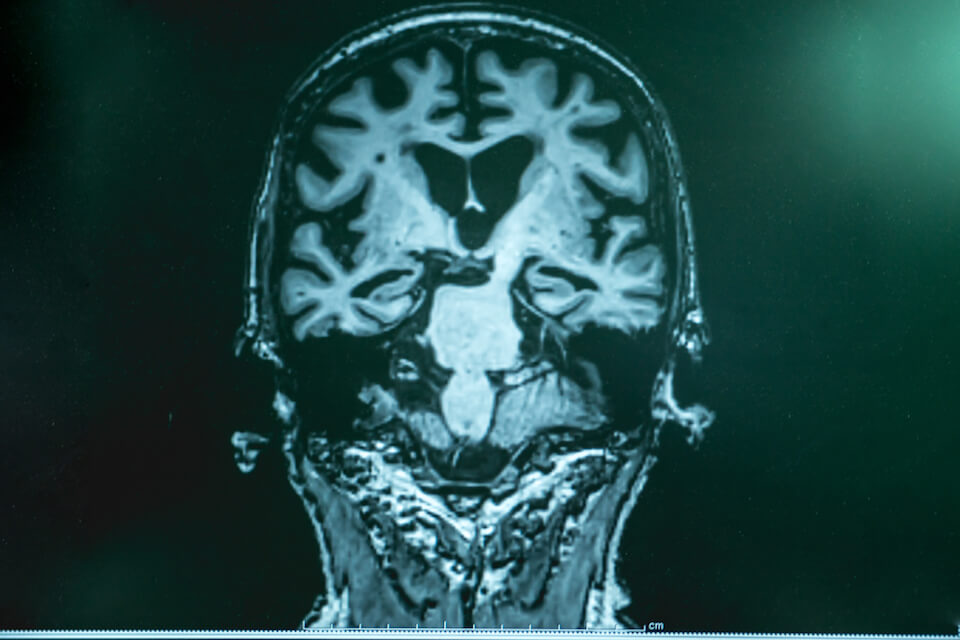

Dr James Everett, Postdoctoral Research Associate at Keele University and a lead author on the paper, said: “Should the magnetic metals identified through this research be linked to the development of Alzheimer’s, they have a potential use as markers for disease diagnosis using techniques such as magnetic resonance imaging (MRI), allowing for pre-clinical disease screening of at-risk cohorts.”